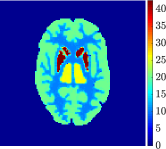

Figure 4, Figure 5, and Figure 6 show the mean images computed over the ten reconstructions obtained by the methods reg-AS-TR, reg-GN, and by the Matlab routine lsqcurvefit implementing a standard Trust-Region-Reflective least-squares algorithm [11, 10]. We used the noise-free IF and the perturbed IF with and of noise, respectively. Figure 7 contains mean and standard deviation values of the kinetic parameters computed over the ten reconstructions and over each one of the four homogeneous regions, for each one of the three noise levels on the IF.

Finally, Figure 8 represents the last frame of the dynamic PET data reconstructed with the mean parametric values returned by reg-AS-TR, reg-GN, and lsqcurvefit, with respect to the noise-free, 10-noise, and 20-noise IFs.

In general, reg-AS-TR and lsqcurvefit seem to provide similar mean reconstructions, although uncertainties associated to lsqcurvefit are significantly bigger. On the other hand reg-GN seems to systematically underestimate the parameter values within region . Furthermore and as expected, for all methods the quality of the parametric reconstructions deteriorates with increasing noise levels; this is more clear from the and parametric images, probably due to the different sensitivities of the data with respect to the model parameters [37]. In reg-GN and lsqcurvefit some artifacts can be observed at the edges of the homogeneous regions, especially around region and region , whereas the effect of regularization in reg-AS-TR results in a reduced presence of artifacts while the structure of the regions is preserved. This general trend is confirmed by the error-bar plots of Figure 7. Finally, the frames in Figure 8 corresponding to reg-AS-TR show a significant improvement of the image quality with respect to what is provided by the other two approaches.